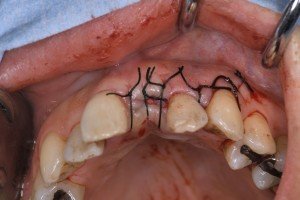

3か月後に2次オペを行い、4か月後に補綴予定です。

オペ終了時の所見です。